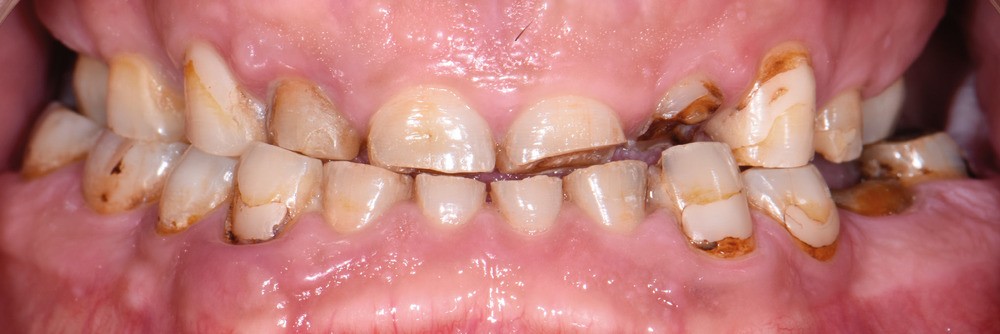

Au vu du contexte para-fonctionnel et de l’étendue de la perte tissulaire, des coiffes périphériques minimalement invasives ont été choisies afin de restaurer l’esthétique et la fonction. Actuellement, aucun consensus n’est fait sur le choix du matériau d’infrastructure à privilégier. Les matériaux hybrides usinables présentent des propriétés mécaniques, physiques et biologiques intéressantes en contexte d’usure sévère (e.g., module d’élasticité, résistance à la propagation de fêlures, facilité de réintervention). Une réhabilitation globale avec remontée de dimension verticale d’occlusion (DVO) par l’intermédiaire de coiffes composites renforcés en nano-céramiques est décrite.